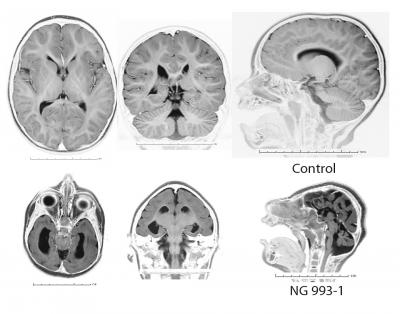

The findings, reported April 28 in the American Journal of Human Genetics , are based on a genetic analysis of in one Turkish family and two Pakistani families with offspring born with the most severe form of microcephaly. The children have brains just 10 percent of normal size. They also lacked the normal cortical architecture that is a hallmark of the human brain. This combination of factors has not been seen in other genes associated with the development of the human brain, the authors note.

The researchers found that mutations in the same gene, centrosomal NDE1, which is involved in cell division, were responsible for the deformity.